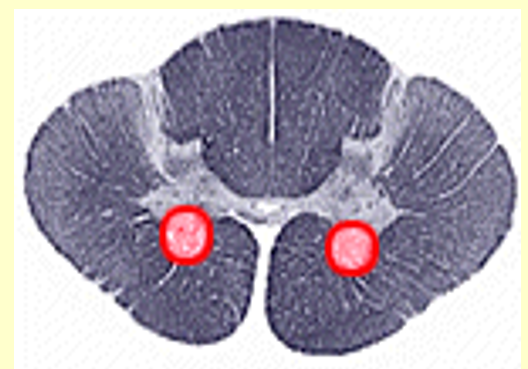

Poliomyelitis